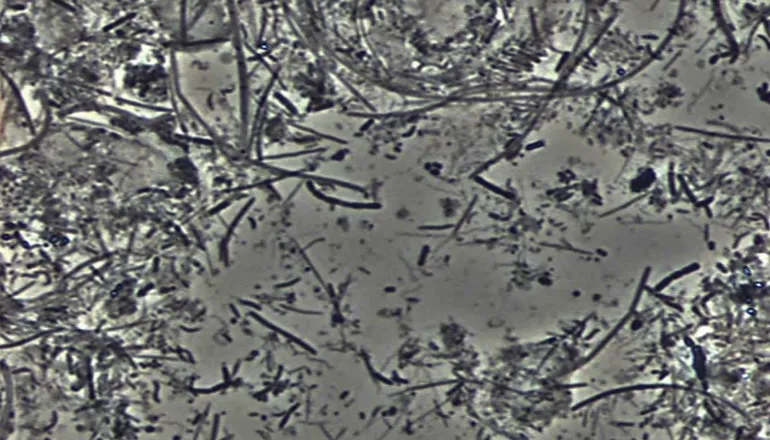

チェックする「位相差顕微鏡検査」

特に遺伝子検査は全国の歯科では限られた医院しか行っておらず、

位相差顕微鏡だけでは発見できない「PG菌」の検出も可能です。

4つの検査

病気の元となる病原菌を解析できる「遺伝子検査」と、口腔の細菌数や内臓の健康状態を調べ、原因を特定する「ガスクロマトグラフ」。さらに「位相差顕微鏡検査」で歯周病になりやすい菌をチェックし、「唾液検査」で分泌物を調べ、組織や細胞をチェックします。